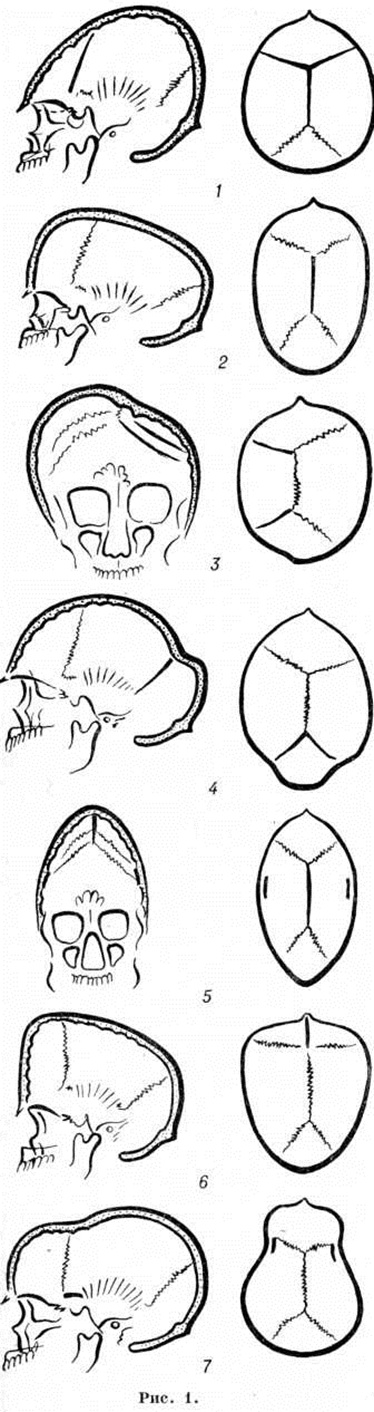

КраниостенозКраниостеноз (craniostenosis; греческий kranion череп + stenosis сужение) — особый вид патологического формообразования черепа, характеризующийся преждевременным синостозом отдельных или всех черепных швов, деформацией черепа, нарушениями структуры его костей, проявляющийся расстройствами зрения и различными симптомами недостаточности функций головного мозга. Краниостеноз может сочетаться с другими пороками развития (синдактилия, мозговая грыжа, заячья губа, волчья пасть, незаращение артериального протока, аномалии развития трахеи и бронхов и так далее). Краниостеноз встречается у 0,005—0,02% новорожденных. Описаны наследственные формы Краниостеноз Этиология и патогенез. Причины преждевременного заращения швов черепа не установлены. Их связывают с различными наследственными и внутриутробными заболеваниями. Патогенез преждевременного заращения швов и всю наблюдаемую при Краниостеноз неврологический симптоматику многие авторы объясняют первичными патологический изменениями в самом черепе и возникающим при этом несоответствии между объёмом внутричерепной полости и объёмом увеличивающегося в размере мозга. Вместе с тем высказывается обоснованное мнение, что раннее заращение черепных швов является только одним из признаков сложной врождённой патологии, в частности первичной патологии в развитии сосудистой системы головы. Изучение особенностей ангиоархитектоники и гемодинамики головы у больных Краниостеноз выявило аномалии вне и внутричерепных артерий и вен, а также выраженные в различной степени нарушения мозгового кровообращения. Эти нарушения выявляются в двух формах — в развитии венозного застоя с последующим нарастанием повышения внутричерепного давления и в развитии ишемического поражения мозга вследствие врождённых патологический изменений в магистральных артериях головы (смотри полный свод знаний Внутричерепное давление). В пользу сосудистой теории патогенеза Краниостеноз говорят экспериментальные данные, согласно которым у 2—4-дневных кроликов изменения кровообращения головы приводят к преждевременному заращению черепных швов. Клиническая картина. Существует множество классификаций Краниостеноз Однако большинство из них не удовлетворяет клиницистов либо неполнотой, либо громоздкостью, либо неточностью классификационных критериев. Клинико-морфологически различают следующие виды Краниостеноз (рисунок 1): 1) оксицефалия (смотри полный свод знаний Башенный череп) 2) скафоцефалия (ладьевидный череп); 3) плагиоцефалия (косой череп); 4) уступообразный череп (батроцефалия); плоский череп (платицефалия); треугольный череп (тригоноцефалия); 7) узкий череп (лептоцефалия); 8) черепно-лицевой дизостоз (смотри полный свод знаний); 9) акроцефалосиндактилия (смотри полный свод знаний Апера синдром). Каждая из этих форм Краниостеноз может быть как компенсированной, так и декомпенсированной. Длительное время считалось, что механизмы компенсации включаются только в связи с повышением внутричерепного давления. Сторонники сосудистой теории патогенеза Краниостеноз считают, что организм компенсирует имеющиеся сосудистые изменения и декомпенсация может развиваться или по типу «венозной энцефалопатии» или ишемии мозга. Клинически компенсированная форма Краниостеноз проявляется только изменением формы головы. Незначительные явления декомпенсации могут проявляться периодическими головными болями. При выраженной декомпенсации, помимо приступообразного характера головных болей, наблюдаются тошнота, рвота, застойные изменения на глазном дне с переходом в атрофию зрительных нервов или развивается их первичная атрофия, снижается зрение. Появляются признаки поражения и других черепно-мозговых нервов, изменяются физиологический рефлексы, нередко возникают эпилептические припадки. Изменения интеллекта встречаются относительно редко. Диагноз, как правило, не представляет особых затруднений. Характерный внешний вид больного с необычной формой черепа (рисунок 2) и данные рентгенологическое обследования позволяют установить диагноз без дополнительных исследований. Рентгенологические исследование черепа при Краниостеноз направлено в первую очередь на выявление признаков преждевременного заращения швов и деформаций черепа. На ранних стадиях развития Краниостеноз обнаруживают лишь сужение одного или нескольких швов, чаще всего сагиттального и венечного, и умеренный остеосклероз костных краёв шва, иногда на относительно небольшом протяжении. |